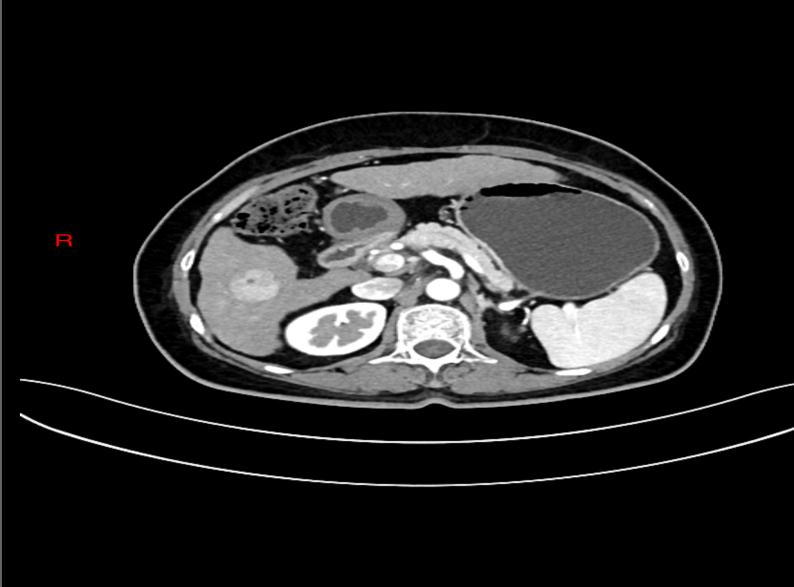

(肝癌增强CT影像)

一个月前,张阿姨因在体检中发现甲胎蛋白(AFP)水平升高,来到西安市红会医院南院区消化内科就诊。施育鹏副主任医师团队高度重视,组织相关检查,明确诊断为原发性肝癌。病灶位于肝内,肿瘤直径小于3厘米,未见肝内其他部位转移或远处转移,属于早期肝癌,具备根治性治疗条件。

1. 术前评估: 通过血液检查(肝功能、凝血功能等)和影像学检查(增强CT/MRI)明确肿瘤的大小、位置、数量以及与重要血管、胆管的关系,判断是否适合做RFA。